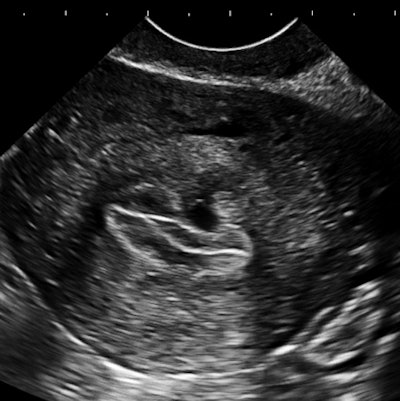

The importance of image contrast is demonstrated in these endovaginal images of a 36-year-old nulliparous woman with heavy and irregular periods due to adenomyosis.

| Above and below: Endovaginal images of a 36-year-old nulliparous woman with heavy and irregular periods due to adenomyosis. |

Adenomyosis (i.e., gland tissue in muscle) occurs when the integrity of the endometrial boundary is disrupted and rapidly growing, vigorous endometrial cells migrate from the city to the myometrial suburbs. Glandular tissue is highly vascularized, leading to the typical 2D Doppler findings with the clinical presentation of heavy, often painful menstruation with clots. There may be small secretory cysts.

The border zone irregularities reconcile the ultrasound findings with pathology and with the classic sign of hysterosalpingography for this condition. This is a grayscale contrast issue. Over the years, I have come to regard contrast as the most important determinant of image quality for all applications of ultrasound.